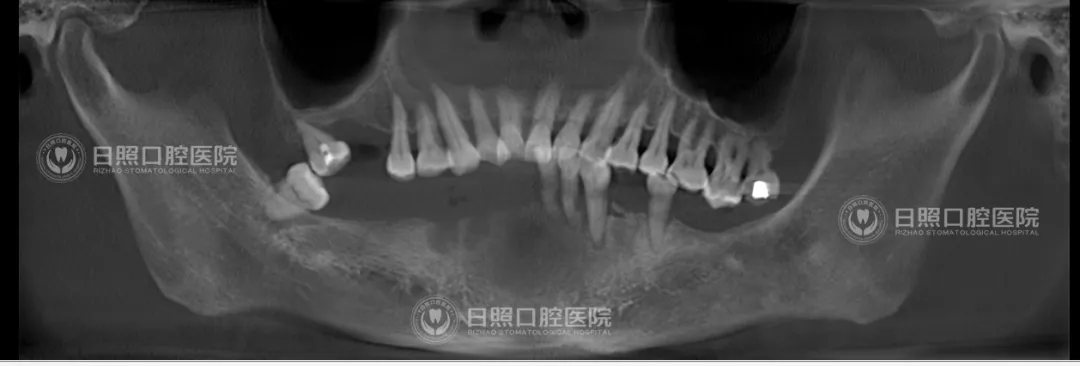

术前,刘大叔下颌仅剩5颗牙齿

王新全主任提前一周为刘大叔设计了种植方案,将他的口腔影像数据通过软件进行三维重建,根据其下颌骨拟种植区骨量条件规划设计种植体路径,手术当日,拔除了刘大叔下颌松动的4颗牙齿,随后,王新全带领种植团队将6颗种植体逐一植入,实现6个位点的精准种植,手术过程约2个小时,种植完成后当日,即为刘大叔试戴、固定预设计制作的即刻义齿。